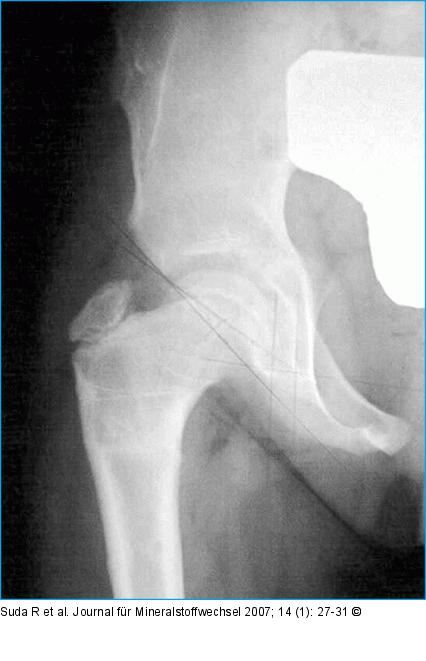

Abbildung 6a-b: Femurosteotomie Zustand nach intertrochantärer varisierender Femurosteotomie mit simultaner Beckenosteotomie nach Salter bei einem 7jährigen Mädchen: (a) postoperatives Röntgenbild, (b) 2 Jahre postoperativ. Der Femurkopf zeigt eine sphärische Ausheilung bei guter Pfannenüberdachung. |

Zustand nach intertrochantärer varisierender Femurosteotomie mit simultaner Beckenosteotomie nach Salter bei einem 7jährigen Mädchen: (a) postoperatives Röntgenbild, (b) 2 Jahre postoperativ. Der Femurkopf zeigt eine sphärische Ausheilung bei guter Pfannenüberdachung. |